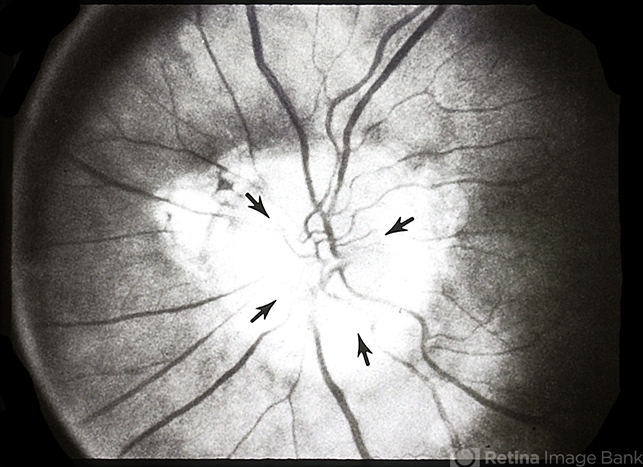

By From the Collections of Thomas M. Aaberg, MD and Thomas M. Aaberg Jr., MD

- peripapillary staphyloma

- Recessed several diopters.